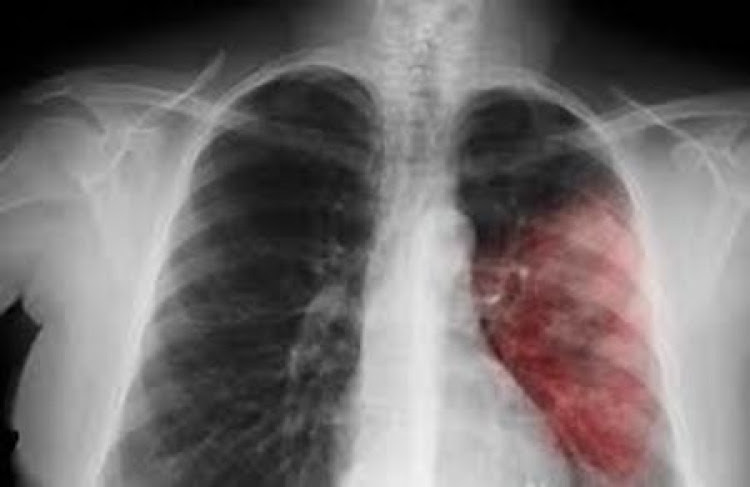

Асимптоматична пневмония - тихият убиец

Много хора погрешно смятат, че пневмонията винаги е придружена от висока телесна температура, болка в белите дробове и силна кашлица. Това заболяване обаче може да протече безсимптомно и за да се избегнат усложнения е важно да го разпознаете навреме. Вижте кои симптоми трябва да ви алармират, че нещо не е наред.

Това заболяване не може да се нарече напълно безсимптомно. Вместо кашлица и висока температура, пациентите изпитват понижаване на настроението, умора и задух. Тези симптоми лесно могат да бъдат сбъркани с нормалната умора. Също така, тревожните симптоми на пневмония включват: - прекомерно изпотяване; - постоянна жажда и липса на апетит; - задух или учестено дишане; - болка под долните ребра; - често главоболие. Един от тревожните (но не винаги възникващи) сигнали за пневмония може да бъде суха кашлица, която не преминава дълго време.